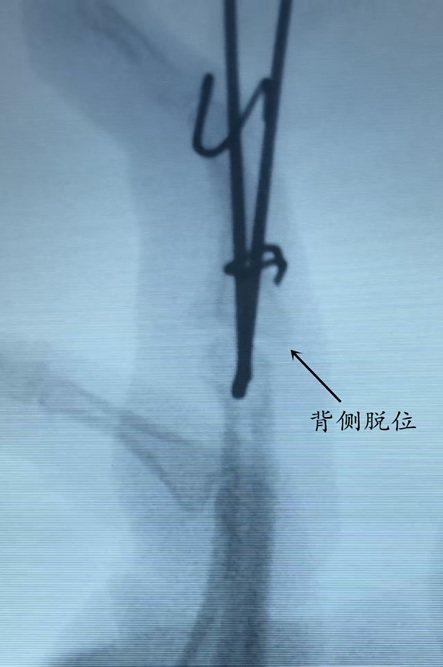

该患者因外伤导致环指PIP关节骨折,伤后自行使用手指夹板固定,保守治疗长达3个月,最终出现手指严重僵硬,关节活动受限,严重影响生活质量。曾于当地医院就诊,进行康复治疗后,活动度不仅没有好转,还发现近指间关节向背侧脱位,患者多方求医后来到我院就诊,手足及显微外科宋俊杰主任团队详细查体、评估影像学资料后,确诊为环指PIP关节陈旧性骨折脱位合并关节僵硬。

针对患者病史长、关节僵硬重、开放性手术创伤大,效果不确切,宋俊杰主任团队经过周密讨论,决定采用自制弹性外固定架进行治疗。

该固定架兼具稳定支撑与弹性微动特点,在有效复位、维持关节对位的同时,可逐步牵拉松解粘连软组织,实现“边固定、边锻炼、边恢复”,避免传统硬固定带来的二次僵硬,尤其适用于陈旧性关节损伤恢复期治疗。